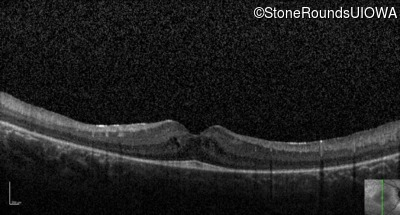

Optical Coherence Tomography - Left - 20/40 -1

Exemplar / OCT Stack